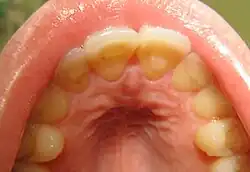

Loss of enamel (acid erosion) from the inside of the upper front teeth as a result of bulimia | |

People with bulimia are at a higher risk to have an affective disorder, such as depression or general anxiety disorder. One study found 70% had depression at some time in their lives (as opposed to 26% for adult females in the general population), rising to 88% for all affective disorders combined.[24] Another study in the Journal of Affective Disorders found that of the population of patients that were diagnosed with an eating disorder according to the DSM-V guidelines about 27% also suffered from bipolar disorder. Within this article, the majority of the patients were diagnosed with bulimia nervosa, the second most common condition reported was binge-eating disorder.[25] Some individuals with anorexia nervosa exhibit episodes of bulimic tendencies through purging (either through self-induced vomiting or laxatives) as a way to quickly remove food in their system.[26] There may be an increased risk for diabetes mellitus type 2.[27] Bulimia also has negative effects on a person's teeth due to the acid passed through the mouth from frequent vomiting causing acid erosion, mainly on the posterior dental surface.